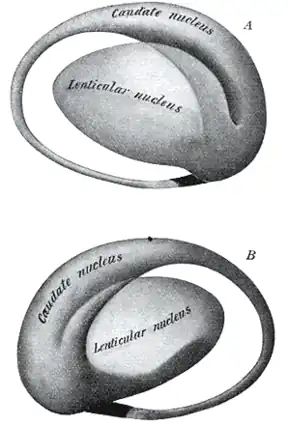

Putamen and globus pallidus make up the lentiform nucleus. | |

Two views of a model of the striatum (i.e. lentiform nucleus plus the caudate nucleus) of the right cerebral hemisphere: A, lateral aspect; B, medial aspect | |